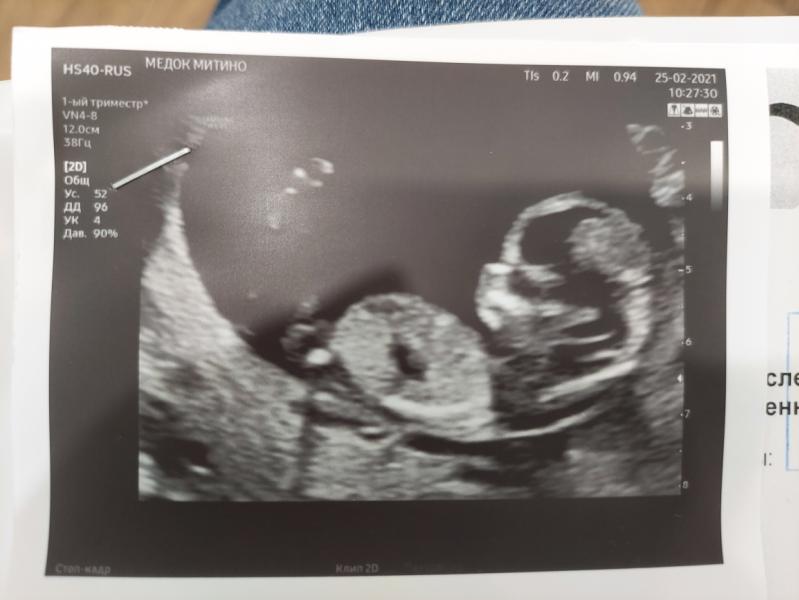

Прошел первый скрининг (ровно в 12 недель), все показатели отличные, ктр 5,4 см, идем точно в срок)

Малыш дисциплинированный, попросили не дергаться, так сразу замер и дал все замерить.

Предположили по половому бугорку мальчика, но на таком сроке сказала еще неточно, может уйти. Бывало ли у кого, что в итоге потом сказали девочку?))